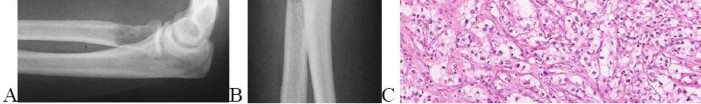

A 15-year-old male presents with deep knee pain awakening him at night. Radiographs show a permeative destructive lesion in the distal femoral metaphysis with a 'sunburst' periosteal reaction and Codman's triangle.

Biopsy confirms high-grade conventional osteosarcoma. What is the most critical prognostic factor for long-term overall survival in this patient?

Explanation

For localized high-grade osteosarcoma, the most important prognostic indicator is the histologic response to neoadjuvant chemotherapy. This is evaluated during the definitive resection. A 'good response' is typically defined as greater than 90% or 99% tumor necrosis. Patients who achieve this level of necrosis have a significantly improved disease-free and overall survival rate compared to 'poor responders' who have extensive viable tumor cells remaining.